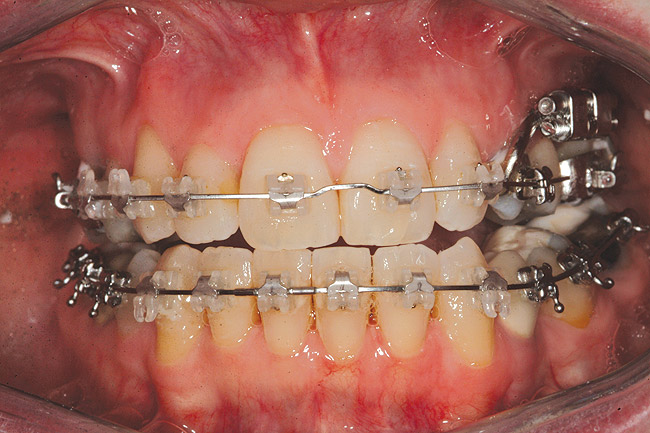

Fig 2 (and Fig 3). Corticotomy SFOT. The patient presented with unesthetic anterior bridgework that was placed at age 14 to compensate for congenitally missing Nos. 7 and 10.

Figure 2

Fig 4. Note gingival inflammation caused by biologic width violation. Provisional restorations were placed on Nos. 6, 8, 9, and 11, and corticotomies were performed from Nos. 3 to 14.

Figure 4

Fig 5. One week postsurgery with mesial buildups on Nos. 5 and 12 and thin pontics on archwire to conceal spaces during closure.

Figure 5